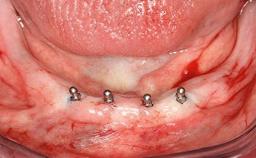

After the placement of three diameter-reduced two-piece implants the bone is augmented with autologous bone chips and DBBM particles to enlarge the crest volume. The surgery is completed with the application of two membrane layers and primary wound closure.